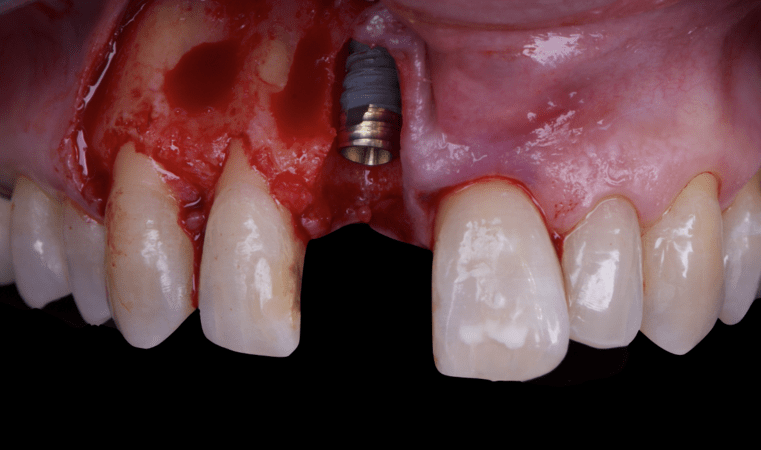

The surgical protocol began with the atraumatic extraction of tooth 1.1 to preserve as much of the alveolar socket as possible. Immediately following extraction, an N1 implant was placed into the socket using a guided surgical approach to ensure ideal three-dimensional positioning. The “one abutment one time” technique was applied to minimize soft tissue manipulation during the healing phase, which is particularly important in esthetic areas.

Given the significant buccal defect, guided bone regeneration (GBR) was performed simultaneously. A mixture of autologous bone and creos™ xenogain™ was applied to the defect and covered with a resorbable creos™ membrane to restore ridge width and support the buccal contour. In addition, a connective tissue graft was harvested and placed in the vestibular region to increase the thickness of keratinized mucosa. This combined approach addressed both hard and soft tissue deficiencies, providing the biological foundation for a stable and esthetic outcome.